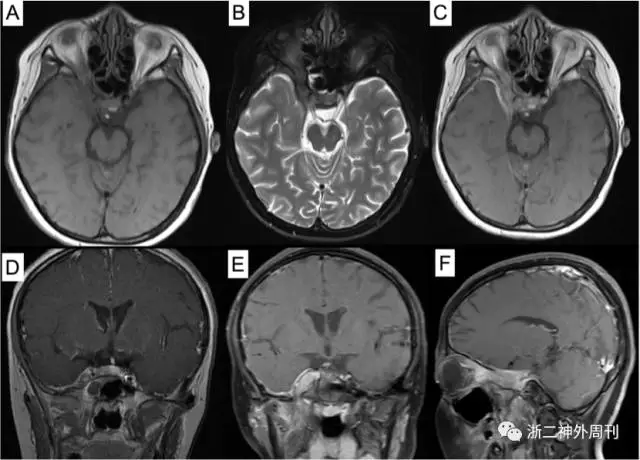

患者,女,11岁,因“头痛3月余,面部浮肿10天”入院。患者3月余前无明显诱因下出现头痛,无恶心呕吐,无畏寒发热,无四肢抽搐等。遂至我院儿科就诊,查CT及MRI示:右眶尖-海绵窦-颞下窝病变,考虑炎症性病变可能,肿瘤不能除外(图1)。今为求进一步诊治,拟以“海绵窦肿瘤”收住入院。

图1. 术前MRI检查:A)T1加权轴位;B)T2加权轴位;C)增强像轴位;D-E)增强后冠状位和F)矢状位示右眶尖-海绵窦-颞下窝病变,呈等T1、略长T2信号,增强后明显强化,邻近脑膜增厚伴强化。